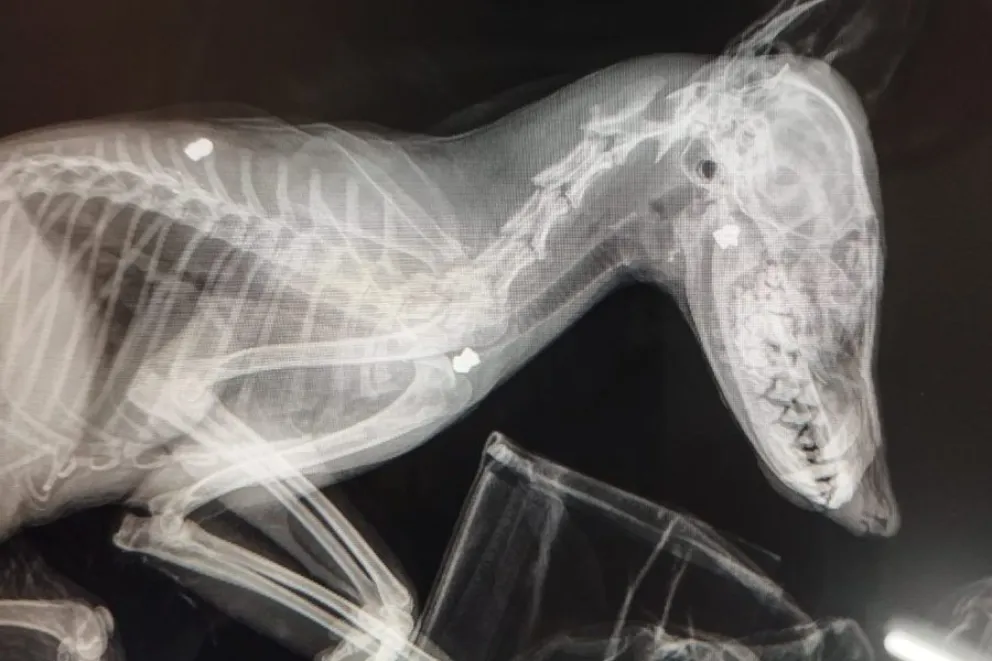

Tiene tres balines en el cuerpo

El equipo de radiografía que tiene la clínica veterinaria del Centro de Conservación de Vida Silvestre (CCVS) permitió detectar balines de vieja data en el cuerpo del animal. El ejemplar sufrió aparentemente un atropellamiento vehicular y tiene pronóstico reservado.

“No pudo determinarse si efectivamente lo atropellaron o lo dedujeron a partir de la parálisis de su tren posterior. Por ello le realizamos radiografías y nos encontramos con balines de vieja data debajo de su piel, encapsulados. Incluso pudimos palpar algunos”, subrayó la veterinaria del Centro de Conservación de Vida Silvestre (CCVS), Andrea Gangone.

“En su piel no había heridas nuevas. Además del lomo, tiene un balín en su mandíbula y otro en la entrada del torax. La medicamos para el dolor y la inflamación. Ni su columna ni sus caderas se ven fracturadas, pero el animal estaba muy decaído y se está recuperando con suero”, remarcó Gangone.